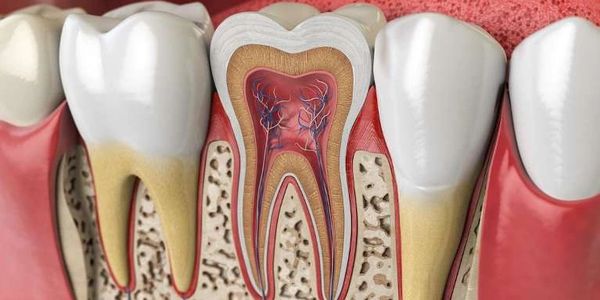

If the cavity has progressed into the nerve chamber, you will need a referral to an endodontist for root canal therapy (RCT). It is possible the pulp is infected, or damaged, needing further treatment.